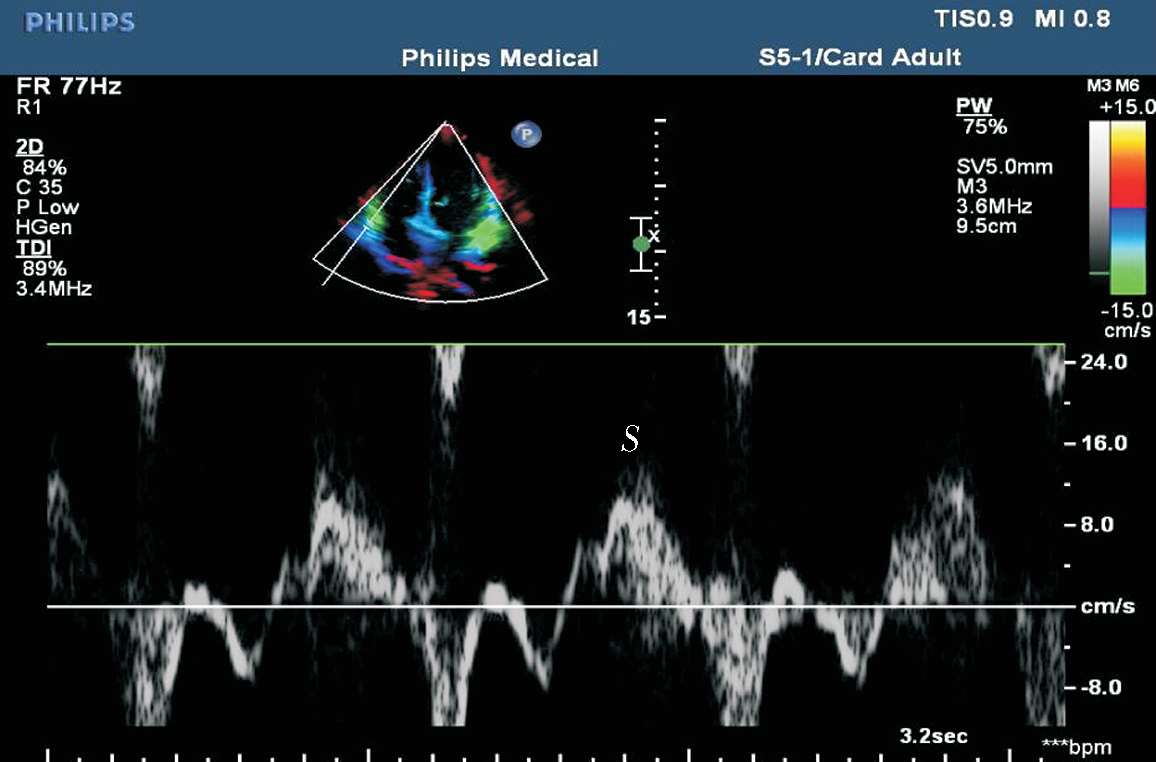

(5)组织多普勒,常以二尖瓣环组织多普勒数据评价左心室收缩功能。二尖瓣环组织多普勒频谱由收缩期正向Sa波、舒张期负向Ea(E′)波和Aa(A′)波组成。Sa波正常值应在5~6 cm/s以上(见图1-37)。

图1-37 二尖瓣环组织多普勒频谱

(2)三尖瓣外侧瓣环收缩期峰值速度(S′)。用组织多普勒测量三尖瓣外侧瓣环获得, S ′<10 cm/s时,提示右心室收缩功能降低(见图1-42)。

图1-42 三尖瓣外侧瓣环收缩期峰值速度